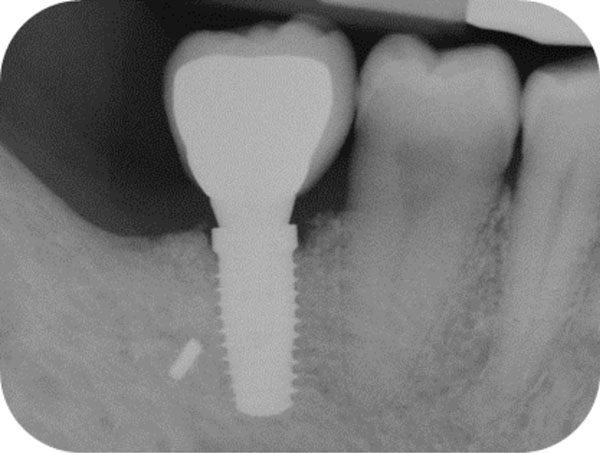

Follow-up x-ray at 24 months displaying the stable maintenance of the peri-implant bone tissue levels and no sign of bone resorption.

After 15 days, the soft-tissue healing was uneventful, and the previously established prosthetic protocol was followed. A single-crown definitive restoration was delivered 1 month (Fig. 11a, 11b). The prosthesis was placed in occlusion, where the occlusal surface was thoroughly modeled, so that it was in contact with reduced areas during laterality and protrusion excursions, in order to reduce the dislocating vectorial components; more contacts were maintained in maximum intercuspation. Follow-up radiographs were taken at 1, 12, and 24 months after prosthesis delivery (Fig. 12, 13, 14).

One year after surgery, clinical examination showed no significant changes in the soft-tissue contours. All follow-up radiographs taken up to 24 months after implant placement showed complete maintenance of the peri-implant bone levels without any sign of bone resorption. The grafted site was perfectly able to support the functional loading of the implant.

The histologic results appear to correlate with the good clinical outcome documented by the intraoral x-rays. Indeed all follow-up controls showed complete maintenance of the peri-implant bone levels without any sign of bone resorption. The healed bone was perfectly stable up to 24 months after bone augmentation, supporting the functional loading of the implant. A possible explanation of the maintenance of bone levels and stability over time is the nearly complete resorption and substitution of the heterologous biomaterial by newly formed functional bone tissue together with the restoration of the masticatory load. The fact that control x-rays maintained the same appearance over time, showing the first implant threads in strict contact with a bone-like area, as far as both structure and radio-opacity are concerned, also suggests that the heterologous bone material may have undergone a remodeling process leading to the osseointegration of the fixture also in the biomaterial-only grafted region.